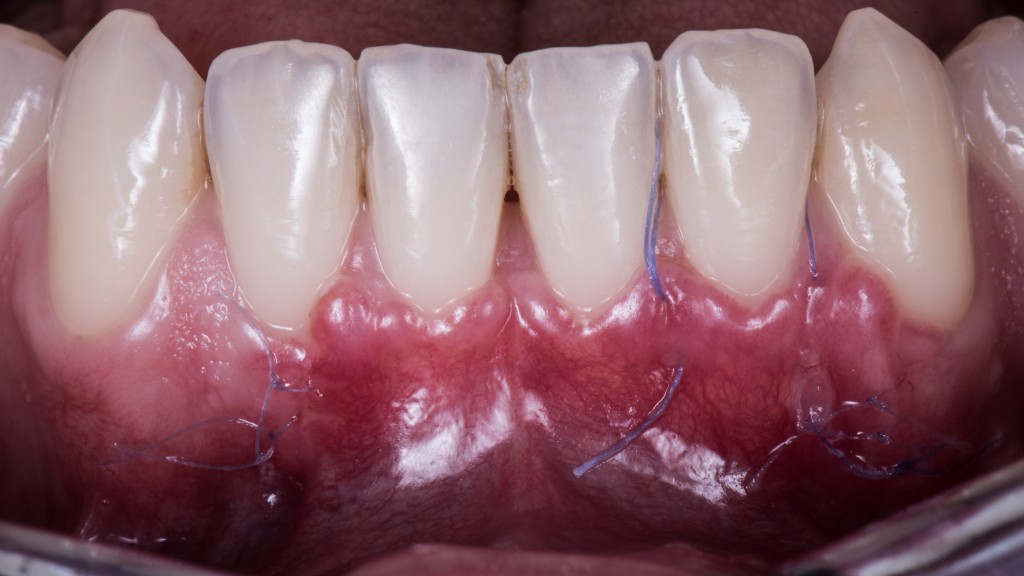

Guarda che bel caso:

Osserva attentamente dove sono le inserzioni muscolari e dove attacca il frenulo. Dicevamo che la zona più merdosa è proprio il quinto sestante perché la mucosa è sempre estremamente sottile ed è l’unico settore anatomico dove c’è un muscolo vero coi controcazzi. Il muscolo mentale.

Se provi a contrarre i muscoletti mimici che trovi nel fornice superiore non ci riesci perché sono insulsi ma se ti metti un dito nel fornice inferiore sotto gli incisivi e corrughi il mento ti rendi conto della roba contro cui devi combattere. Del super malvagio che andrà a tirare sui tuoi punticini 6-0.

Per questo motivo uno dei passaggi fondamentali nell’esecuzione del lembo spostato coronalmente è quello di disinserire le inserzioni muscolari sia dal periostio sia dalla sottomucosa e, in questa zona infame, togliere pure un bel pezzo di muscolo per stare tranquilli.

Questo, associato alle altre due tecniche segrete di cui parleremo nei prossimi articoli, ti consente di arrivare a 15 giorni dall’intervento in questa situazione: